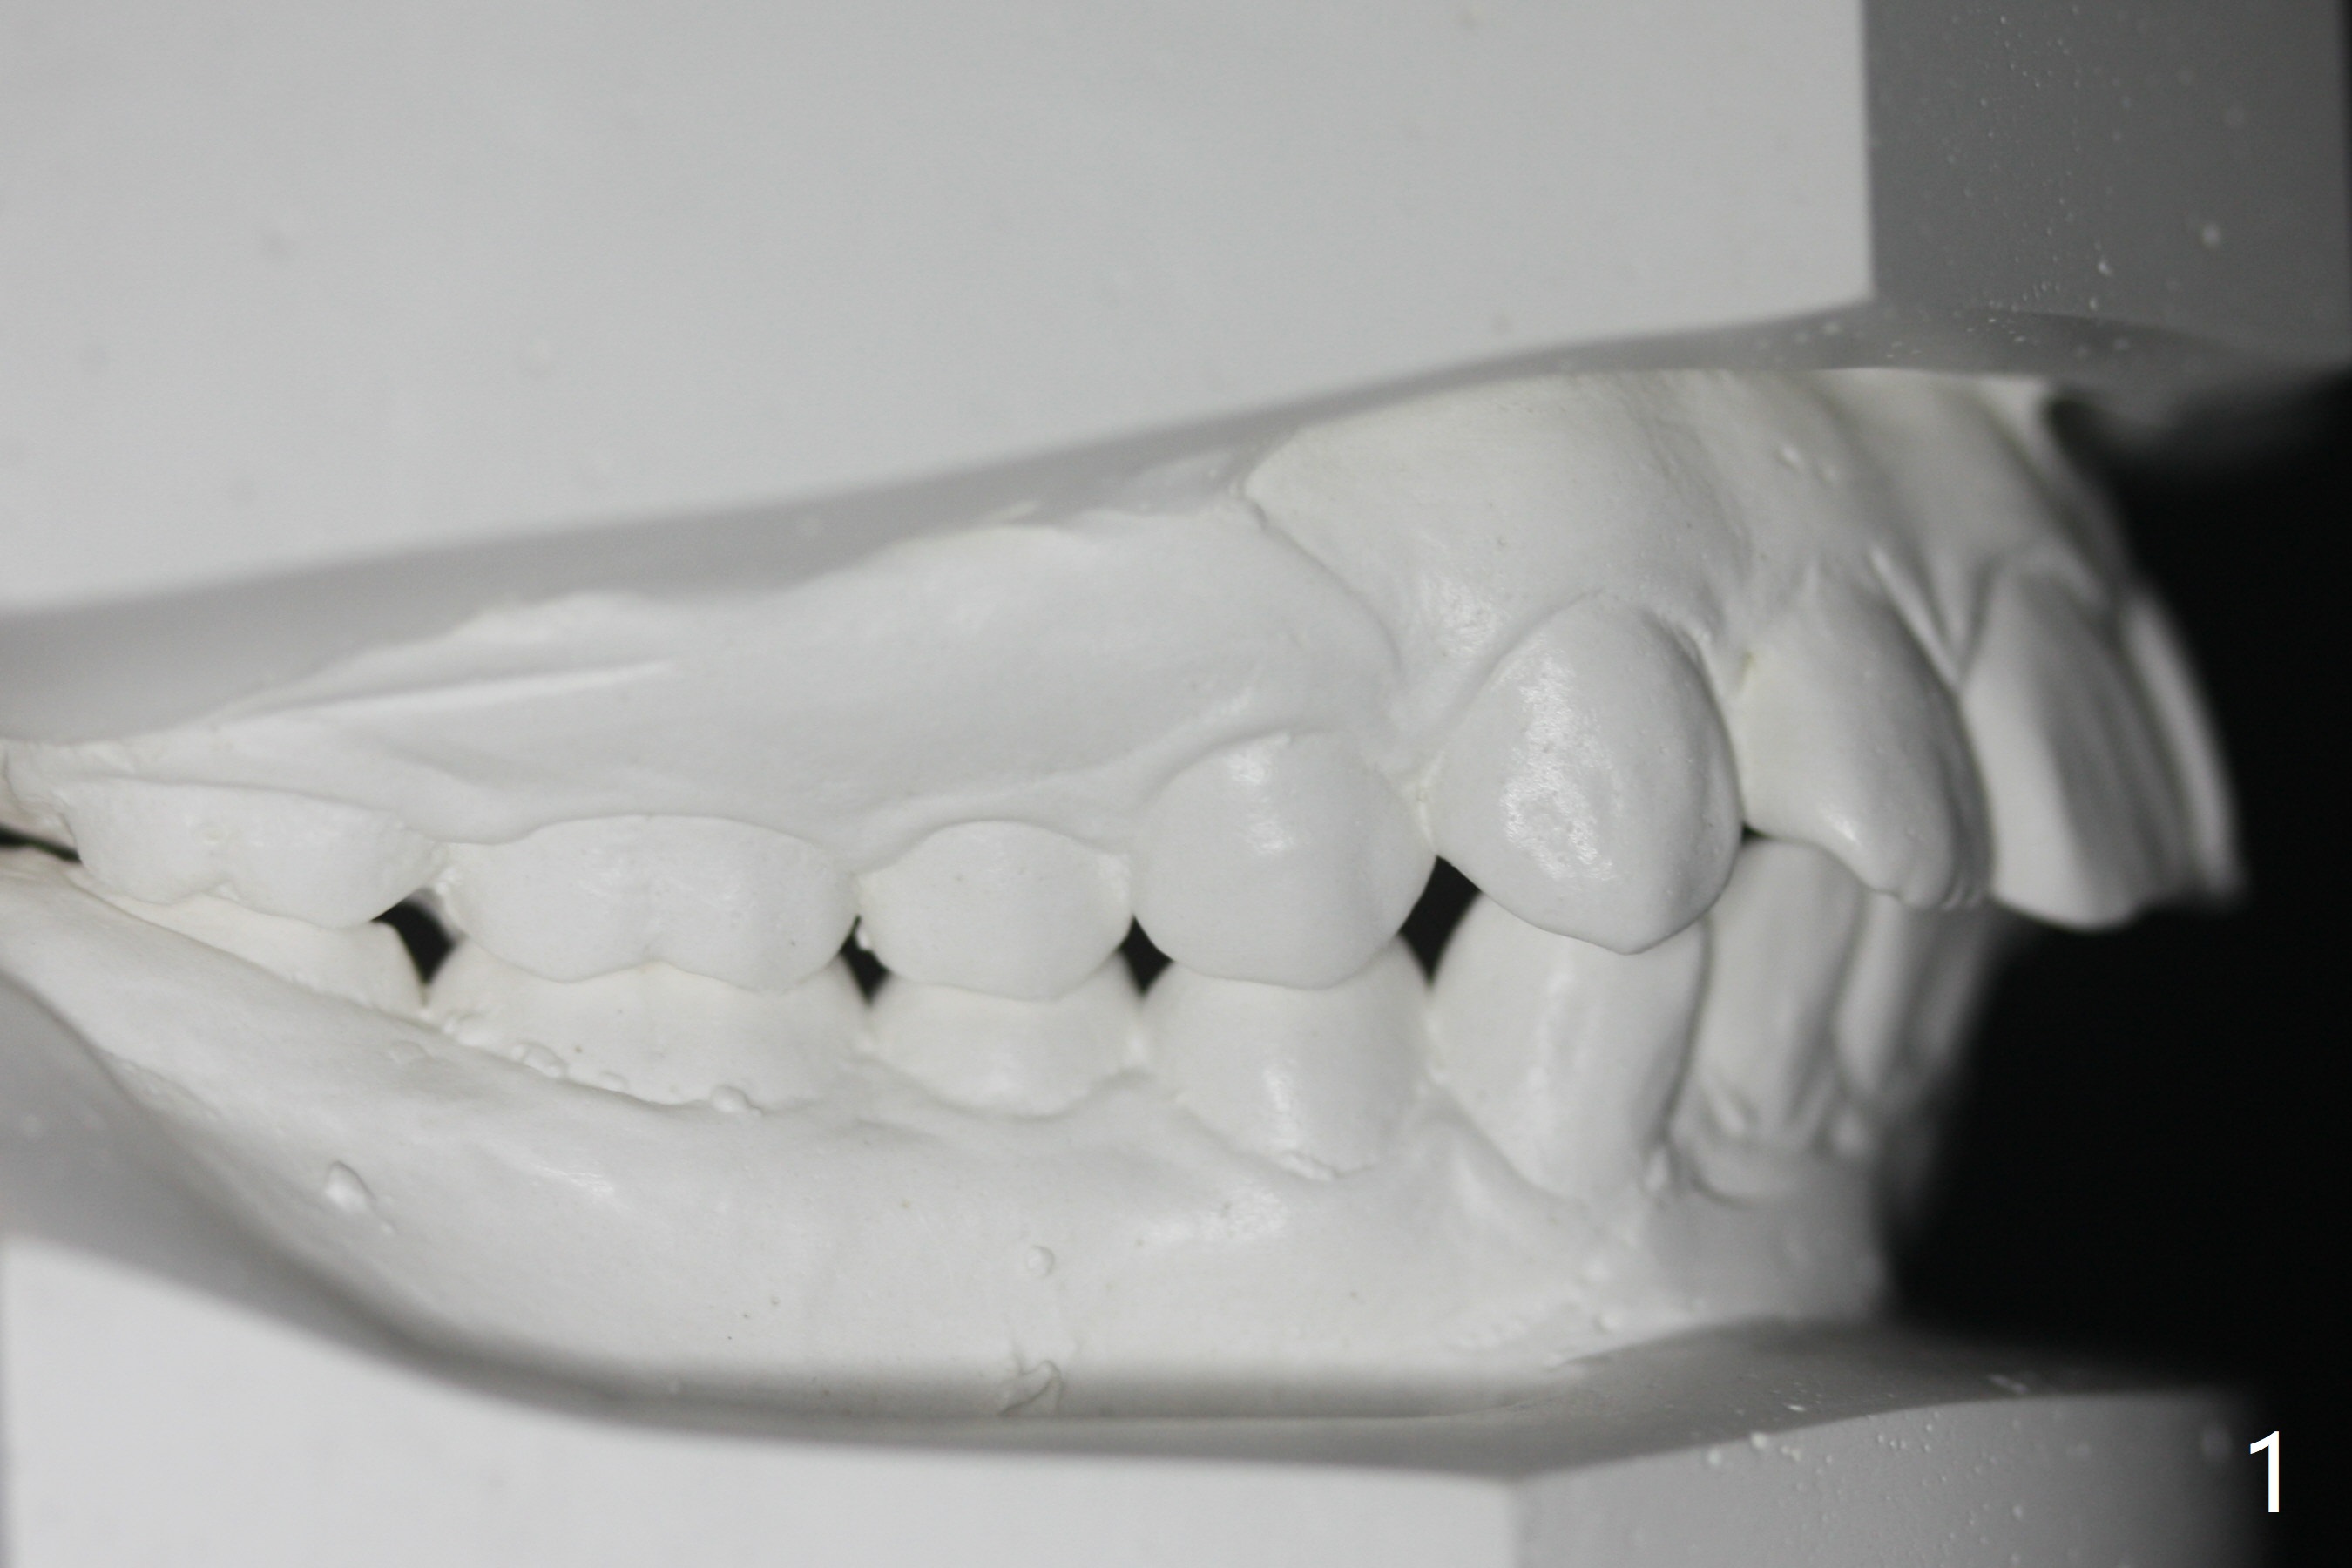

I Malocclusion

The 1st step to correct severe Class II Division I malocclusion (Fig1) is extraction of 4 of the 1st bicuspids (Fig.2 X). Following placement of 16x16 wires, start Class II retraction (Fig.3 red line) as well as distalization of U3 (Fig.4). When canine Class I relation is established (Fig.5 horizontal arrow (using power chain between L3/5)), arch wire sequence should be able to intrude the incisors (vertical arrows). Finally the lower 2nd bicuspid and molars are mesialized (Fig.6 arrow).